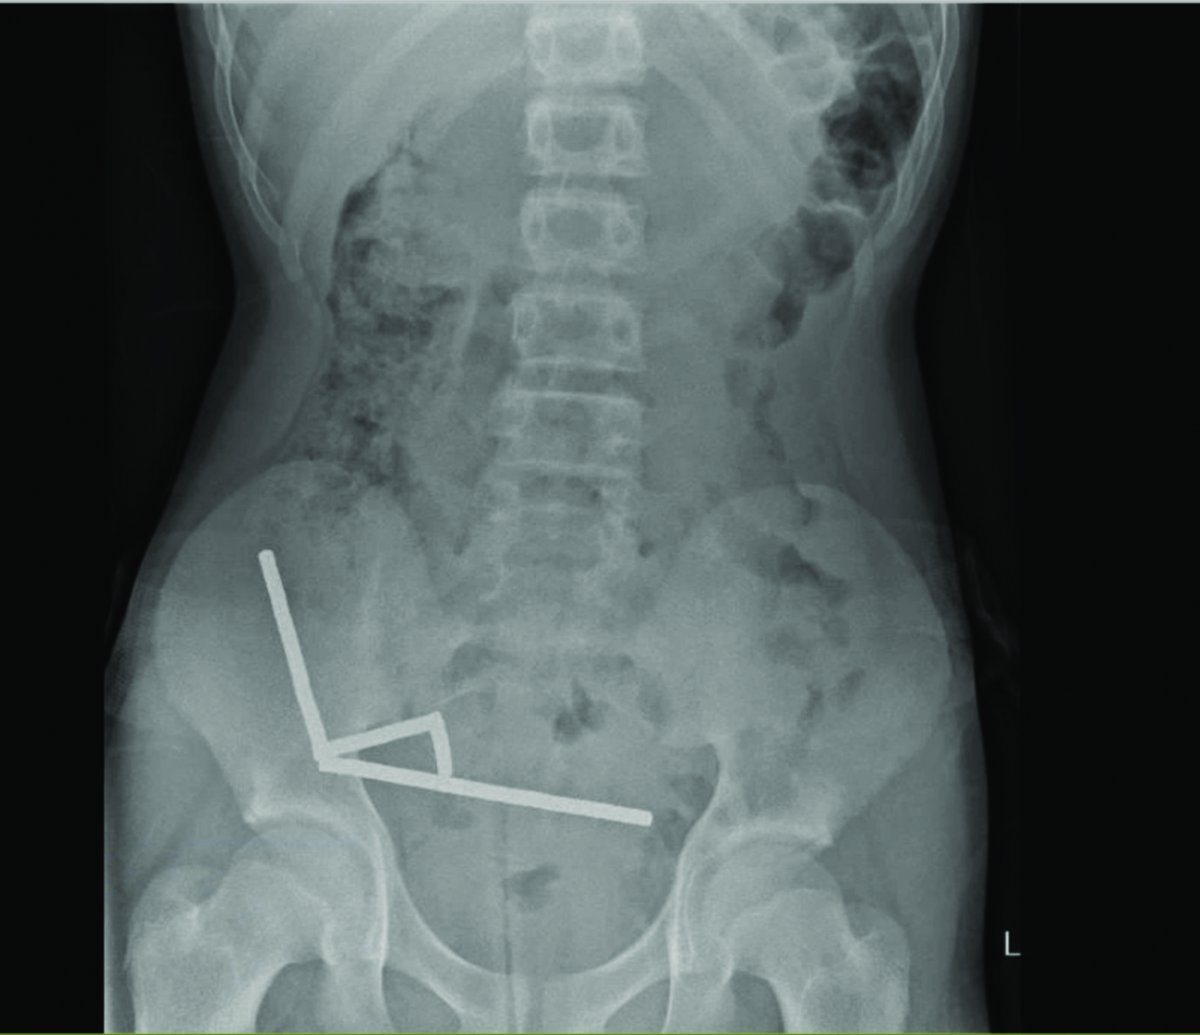

Galéria k článku Chlapec (13) mal neznesiteľné bolesti: Zjedol takmer STO magnetov! Prišiel o kus čreva

Zdroj: New Zealand Medical Journal